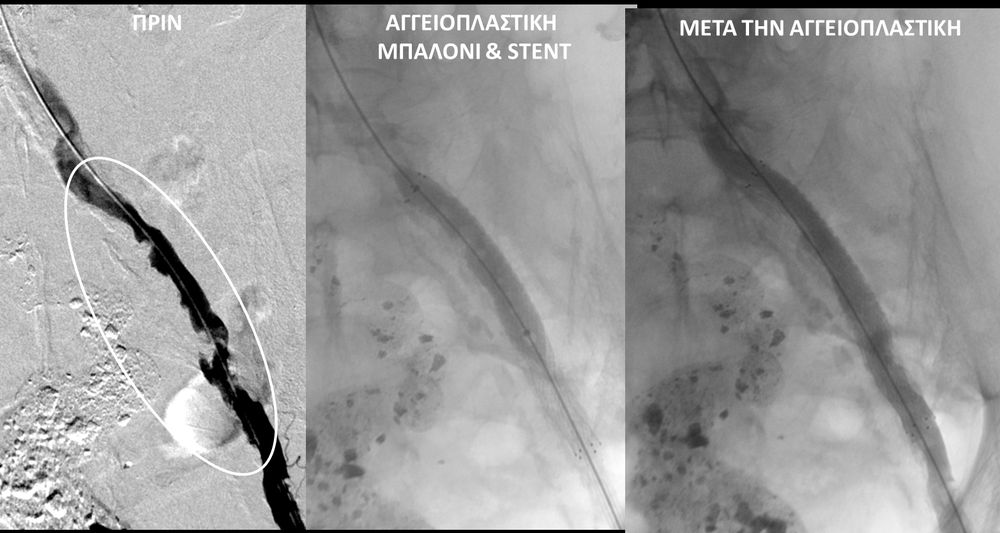

O σακχαρώδης διαβήτης είναι μεταβολική ασθένεια η οποία χαρακτηρίζεται από αύξηση της συγκέντρωσης του σακχάρου στο αίμα (υπεργλυκαιμία) και διαταραχή του μεταβολισμού της γλυκόζης. Ο βαθμός αύξησης της γλυκόζης στο αίμα και η παραμονή των αυξημένων τιμών της για μεγάλο χρονικό διάστημα βλάπτουν, κυρίως, τα μικρά αγγεία, προκαλώντας διαβητική νευροπάθεια, διαβητική νεφροπάθεια, αμφιβληστροειδοπάθεια κ.τ.λ., με σοβαρότατες συνέπειες σε πολλά όργανα-συστήματα.Στην Ελλάδα κάθε χρόνο πραγματοποιούνται 2.000 – 3.000 ακρωτηριασμοί κάτω άκρων, αφού το 4-5% των πασχόντων από διαβήτη εμφανίζει περιφερική αγγειοπάθεια με έλκη ή και γάγγραινα στα πόδια. Σε ποσοστό 80% οι ακρωτηριασμοί θα μπορούσαν να αποφευχθούν και η επεμβατική ακτινολογία μπορεί να βοηθήσει σημαντικά.Η διαδερμική ενδαγγειακή αγγειοπλαστική (percutaneous transluminal angioplasty, PTA) είναι μια ελάχιστα επεμβατική μέθοδος αντιμετώπισης των αρτηριακών στενώσεων ή και αποφράξεων του διαβητικού ποδιού (περιφερικήδιαβητικήαρτηριοπάθεια).